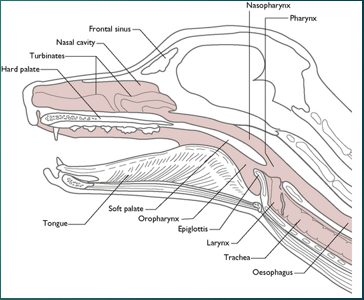

Brachycephalic obstructive airway syndrome in Dogs

Bulldog

Pug

Pekingese

French Bulldog

Boxer

Brachycephalic obstructive airway syndrome in Cats

Persian

Himalayan

Stenotic nares

Narrowing of the nasal passages, this increases resistance, making breathing in and out more difficult for the paitent

Oversized tongue

Tongue is too big for their moth, can push on soft plate

Elongated soft palate

Effects the epiglottis so can aspirate more easily

Hyperplastic larynx

Overgrowth of soft tissue in the larynx, leading to obstruction

Hypoplastic trachea

Trachea is narrower

Brachycephalic obstructive airway syndrome

The problems we see in these breeds are the consequences of trying to move air with all this increased resistance. To breathe they need to move O2 through the resp tract to the lungs, these issues with the soft tissues that we’ve highlighted cause resistance to air flow, this then increases Resp effort and rate to get more air in, this increases the negative pressure which makes the issue worse – negative pressure caused by them trying to overcome the resistance means that we get more resistance, more swelling of soft tissues and thus more negative pressure. We will often see abdominal effort with BOAS breathing.